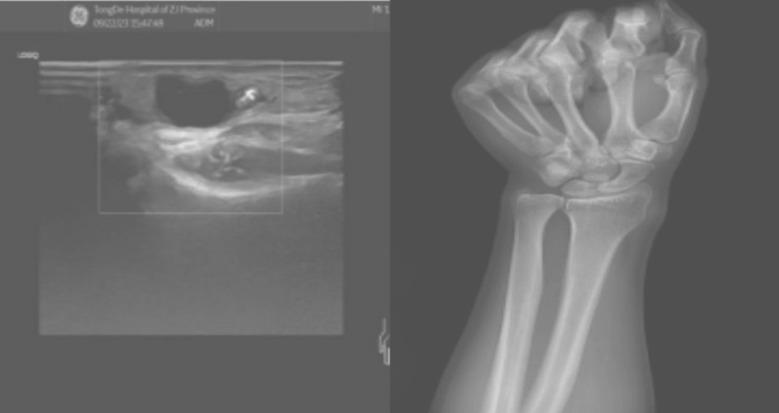

Wrist ganglion cyst enveloping radial artery.

Wrist ganglion cysts typically do not show noticeable symptoms but can affect aesthetics and even compress adjacent blood vessels and nerves. Compression therapy can eliminate cysts. However, caution is needed when treating cysts around the radial artery. This study examined a rare case of a wrist ganglion cyst that, after repeated compression and recurrence, enveloped the radial artery. This not only caused wrist swelling and pain but also increased the difficulty and risk of surgical treatment.